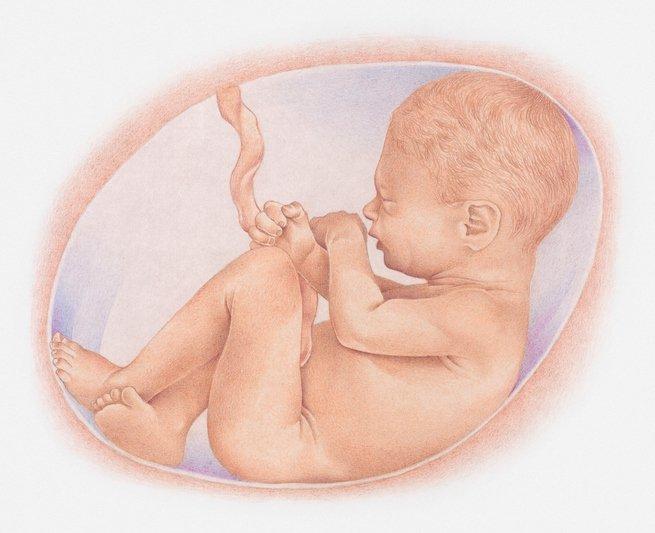

Cairan ketuban adalah cairan berwarna agak kekuningan yang mengelilingi bayi di dalam rahim. Cairan ketuban muncul pada 12 hari setelah pembuahan.

Kemudian sekitar usia kehamilan 20 minggu, air ketuban digantikan dengan urine janin yang ditelan dan dikeluarkan lagi oleh tubuh janin, begitu seterusnya.

Cairan ketuban memiliki fungsi yang sangat banyak bagi bayi. Beberapa fungsi dari cairan ketuban adalah:

- Melindungi janin dari tekanan luar, sebagai bantalan bagi janin

- Membantu mengontrol suhu bayi agar selalu merasa hangat

- Melindungi bayi dari infeksi karena juga mengandung antibodi

- Membantu perkembangan otot-otot pada sistem pencernaan dan pernapasan karena bayi bernapas dan menelan cairan ketuban

- Membantu perkembangan otot dan tulang

- Membantu bayi bebas untuk bergerak.

- Mencegah penekanan pada tali pusar sehingga makanan dan oksigen bisa diantarkan ke janin dengan lancar.

Cairan ketuban yang sehat turut mendukung pertumbuhan dan perkembangan bayi yang sehat dalam kandungan.